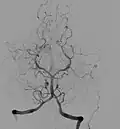

Die hirnversorgenden Gefäße können mit bildgebenden Verfahren, insbesondere mit der Angiografie dargestellt werden. Für die digitale Subtraktionsangiographie wird ein strahlendichtes Kontrastmittel appliziert; während der Durchleuchtung mit Röntgenstrahlen werden die Skelettanteile herausgerechnet. Somit bilden sich nur die kontrastmitteldurchströmten Gefäße ab.

Subtraktionsangiographische Darstellung der vertebrobasilären Hirngefäße